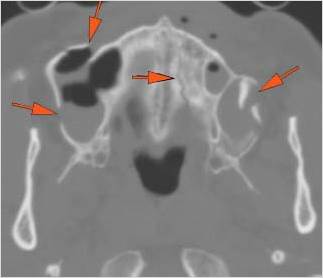

The medial, lateral and posterior maxillary walls are fractured. [Yes/No]

The infraorbital rims and orbital process of the zygoma and/or frontozygomatic suture are fractured. [Yes/No]

The alveolar ridge, premaxilla, and/or the palatine process of the maxillary bones on either side are fractured. [Yes/No]

The hard palate is fractured. [Yes/No]

The pterygoid processes of the sphenoid bone are fractured. [Yes/No]

The mesial naso-orbito-ethmoid complex is fractured. Specifically, there is bony injury of the nasal bones or the frontal process of the maxilla and the medial walls of the orbit are abnormal. [Yes/No]

There is injury of the ethmoid complex. Specifically, the ethmoid roof, olfactory fossa and the cribriform plate are fractured and/or significantly dehiscent. [Yes/No]

The the zygomatic arch, frontozygomatic suture or infraorbital rim are fractured. [Yes/No]

The lateral wall of the orbit is fractured. [Yes/No]

There is fracture of the greater or lesser wing of the sphenoid bone, optic strut and canal, or basisphenoid, in the region of the orbital apex. [Yes/No]